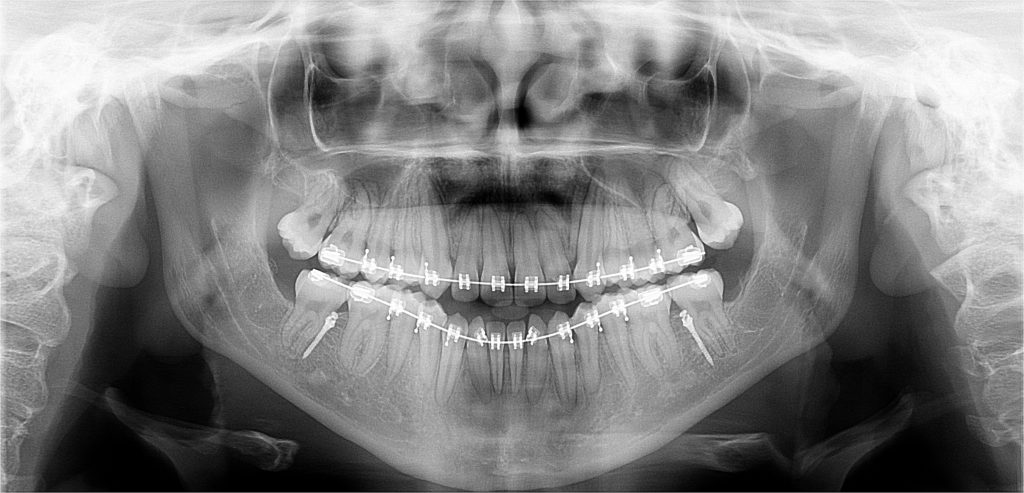

Contamos con el primer y único equipo de Rayos X digital de la ciudad.

Para diagnosticar y tratar las enfermedades orales de manera más eficaz y precisa a nuestros pacientes, y así otorgarles una atención integral y segura, evitándoles viajar cientos de kilómetros a otras ciudades para la toma de estos exámenes. Nuestro equipo de rayos x cuenta con todas las autorizaciones sanitarias para su instalación y desempeño.